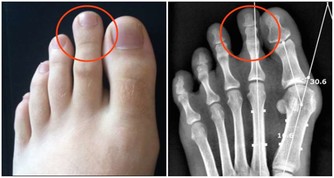

2、指尖翹變

如果發現指甲的前端略微向上翹起,並且形狀呈前寬後窄的樣子,指甲中弧形呈現出凹線性的改變趨勢,這種現象說明身體內部的某一個或者多個器官有炎症,這也是毒素過多的表現之一。器官本身的免疫功能無法抵制住毒素的侵害,產生了炎症。

此外,出現這種現象的患者多數表現為脾氣暴躁,肝火旺盛,這就是肝臟部位毒素過多的緣由之一。肝火旺盛可不僅僅是脾氣大的問題了,還會導致肝臟部位加速衰老,功能衰弱退,繼而引發其它器官的病變。